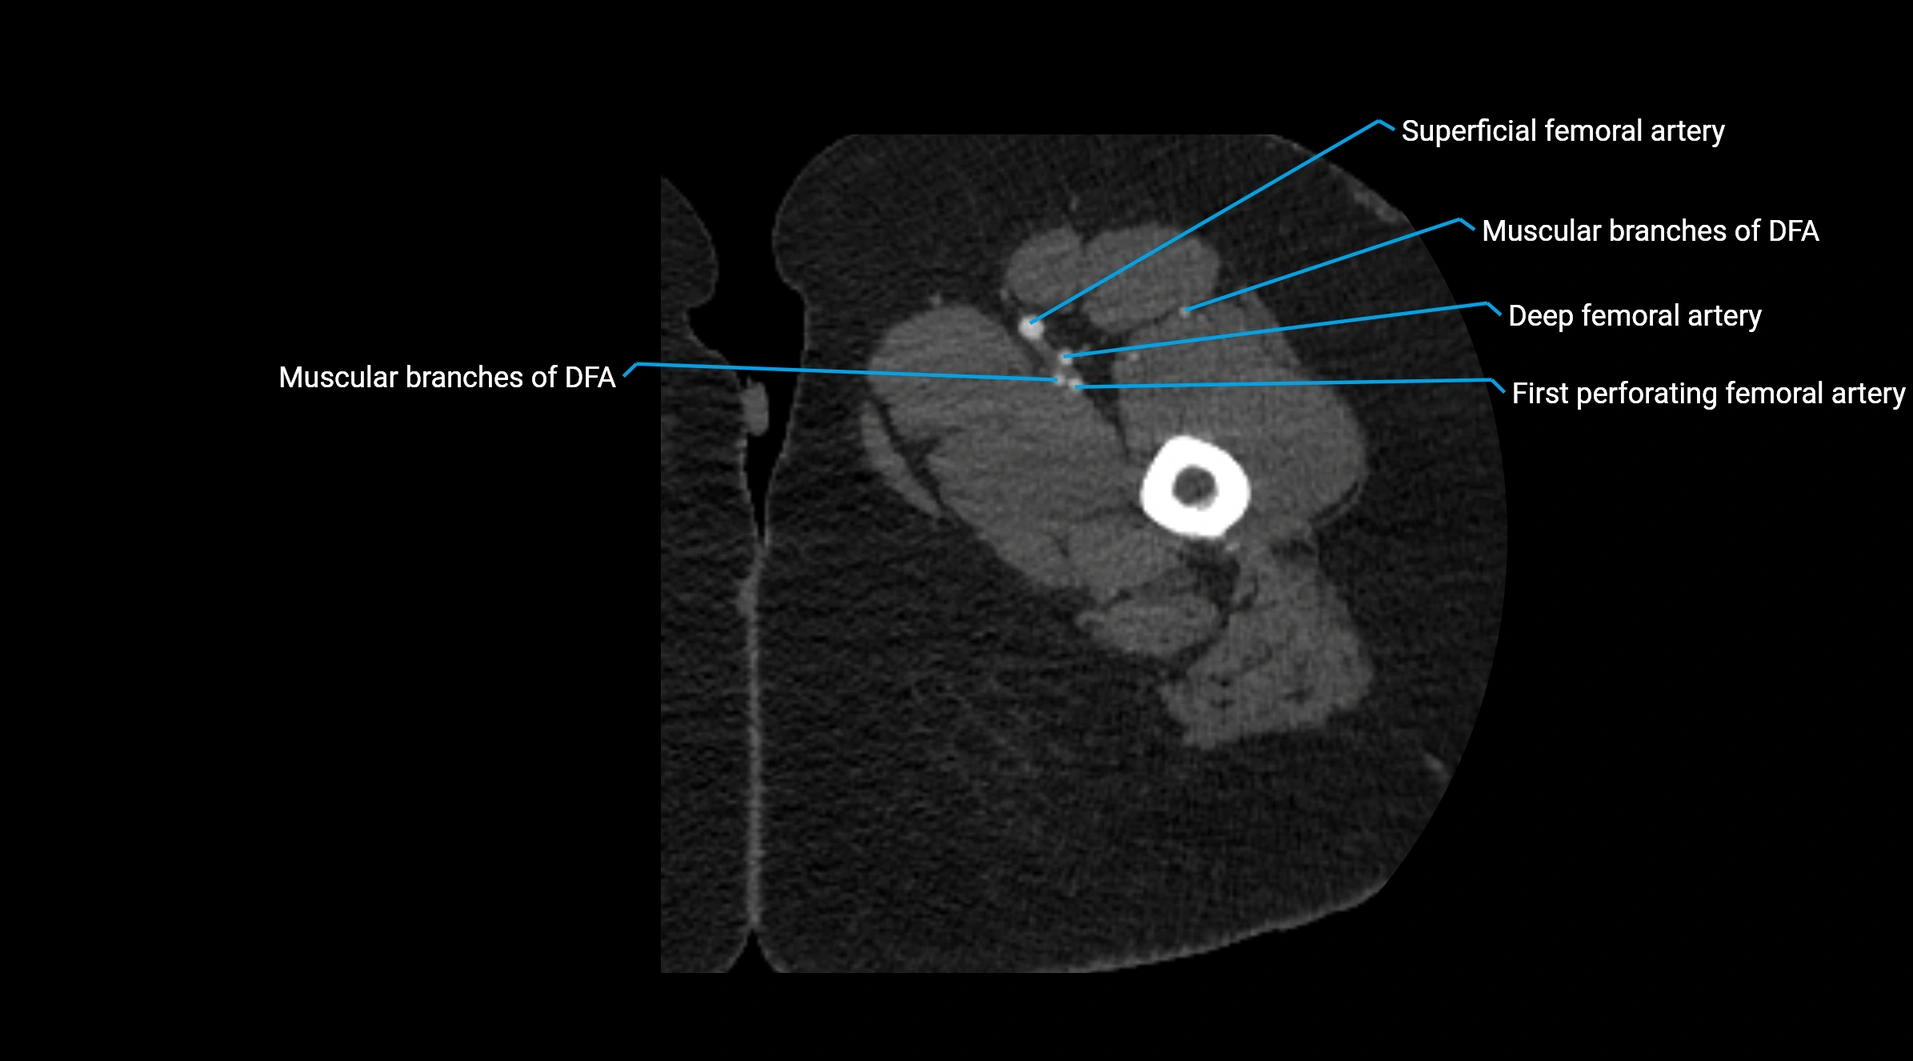

Contrast-enhanced CT (CTA):

• Gold standard for abdominal aortic imaging

• Provides excellent detail of lumen, wall, aneurysm, thrombus, and branch vessels

• Multiplanar and 3D reconstructions help in aneurysm measurement, stent graft planning, and dissection evaluation

• Detects acute rupture, traumatic injury, or occlusion with high sensitivity